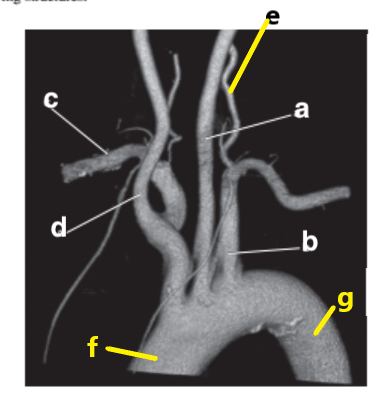

Left vertebral artery

What is letter h ?

Brachiocephalic trunk

What is letter f ?

What is letter a ?

Ascending aorta

What is letter c ?

Hemiazygos vein

Aortic Arch

What is letter g ?

Descending aorta

Left anterior descending artery

What is letter d ?